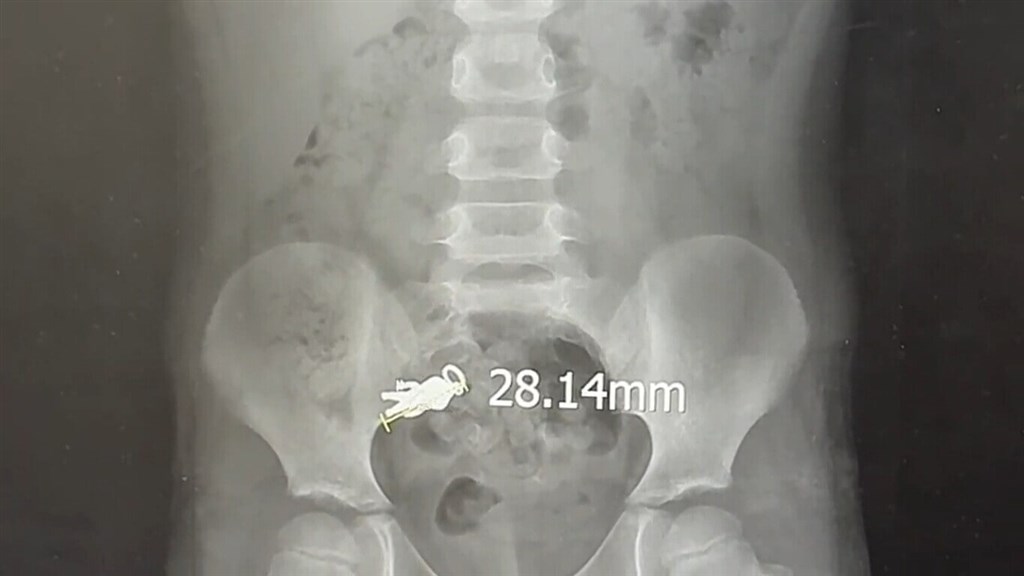

(Sumber Foto : Dokumentasi Rumah Sakit Lotung Poh-Ai, 9 September 2025)

Anak laki-laki itu dibawa ke Rumah Sakit Lotung Poh-Ai, di mana hasil rontgen menunjukkan pernak-pernik pahlawan super Jepang berukuran panjang 2,8 sentimeter dan lebar 1,4 sentimeter itu telah berpindah ke ususnya.

Insiden ini terungkap setelah sebuah unggahan di situs media sosial Threads hari Selasa (9/9) mengungkapkan bahwa anak laki-laki tersebut mengaku telah menelan liontin itu hari Sabtu, disertai gambar rontgen yang diduga menunjukkan figur kecil tersebut di dalam tubuh sang anak.